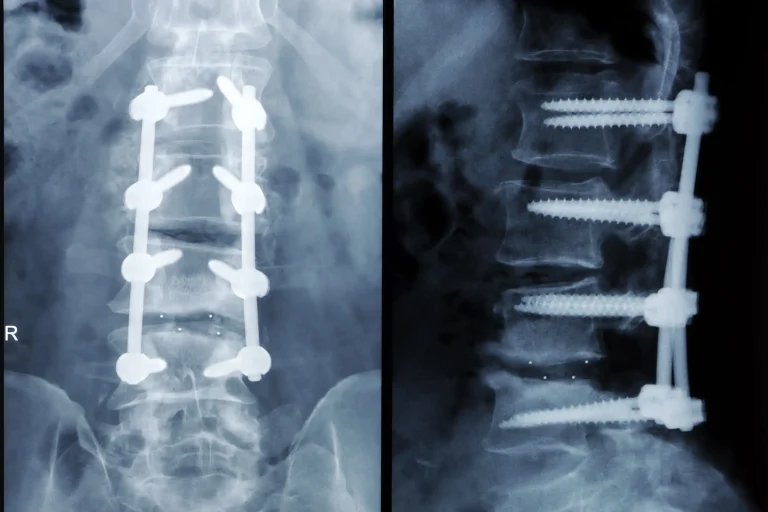

Spinal Fusion is a highly invasive procedure that permanently fuses vertebrae using screws, rods, and cages. It eliminates natural spinal motion, causes adjacent segment disease in the majority of patients, and over 90% require additional surgery. Discover safer, minimally invasive alternatives.

Spinal Fusion Surgery X-ray images showing spinal fusion with screws and rods.

X-rays of spinal surgeries showing metal screws and rods in the spine.

90%+ Need Additional Surgery